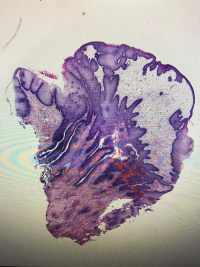

尿道肉阜

性别

女

年龄

62

临床诊断

一般病史

尿道流血3年

标本名称

大体所见

灰白组织一块,大小1.2✖️0.8✖️0.8,切面灰白,半透明,质软

符合:

尿道肉阜。